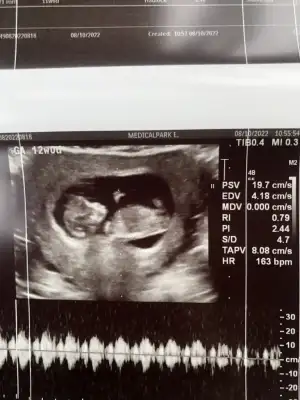

doktor da 11+3 te ki kontrolüne göre bişey söylemek için erken ama kızımsı duruyor demişti

doktor da 11+3 te ki kontrolüne göre bişey söylemek için erken ama kızımsı duruyor demişti değerler de normal gözüküyor sanırım.

değerler de normal gözüküyor sanırım.

bende de 59 free beta hcg ve buna göre sözde kız. Papp a değeri 2.35. Doktor problem yok demişti. Seninkinde de yoktur.